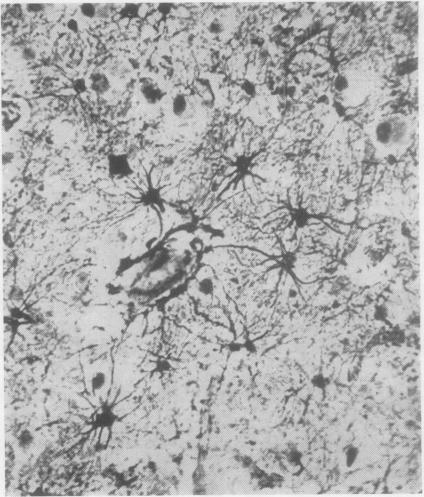

The pathology and chemistry of a case of gargoylism.

J Clin Pathol. 1956 Nov;9(4):305-15. doi: 10.1136/jcp.9.4.305.